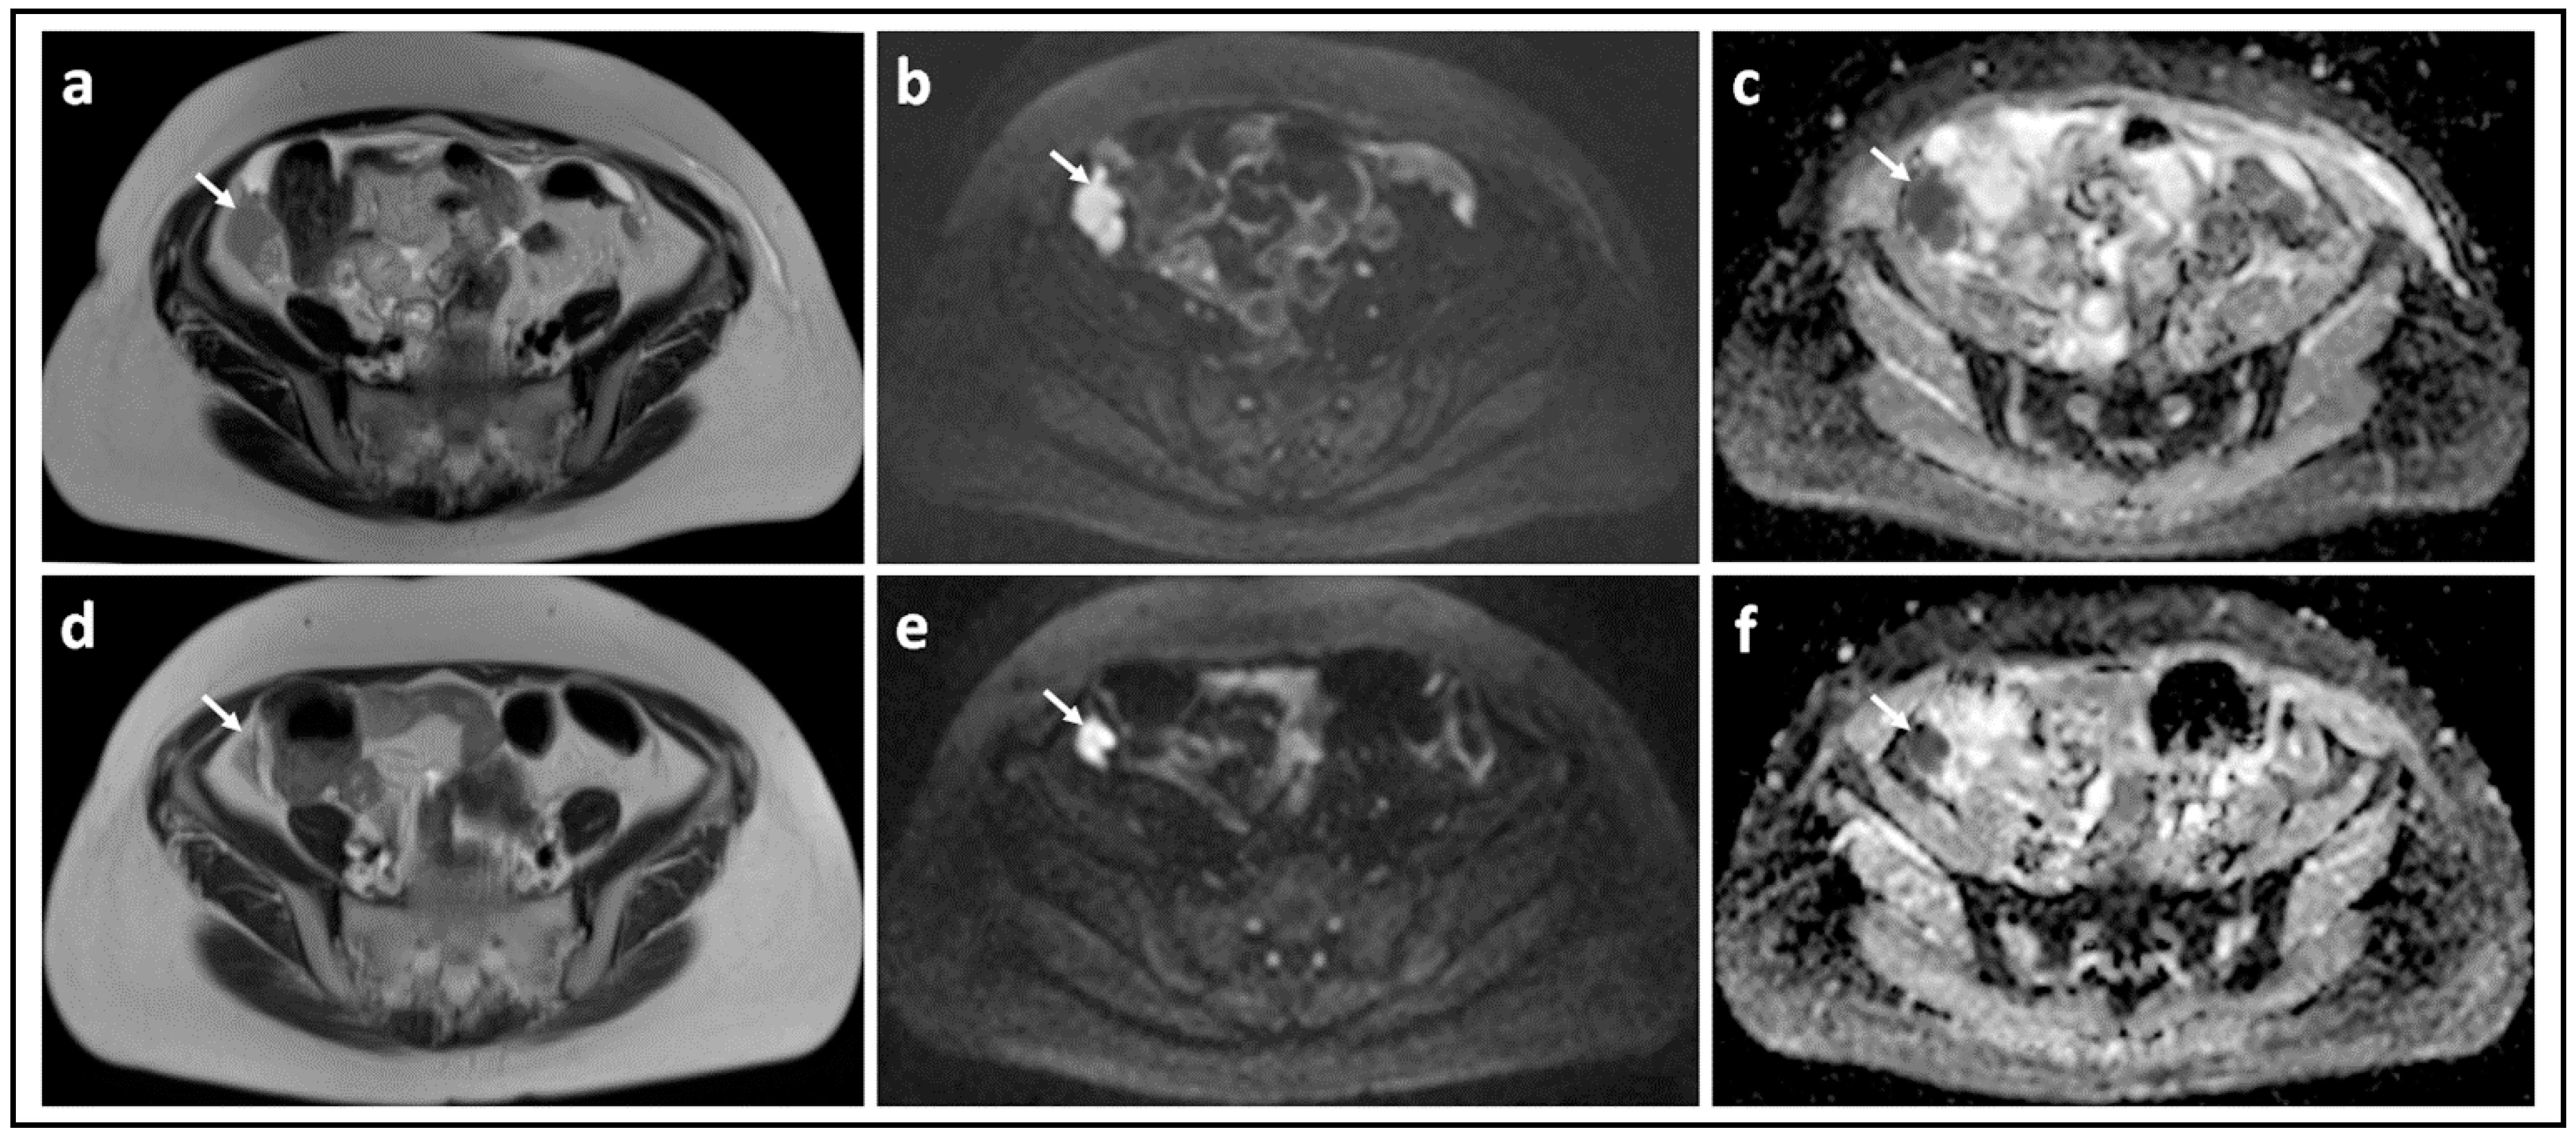

- Michielsen, K.L.M.; Vergote, I.; Dresen, R.; De Beeck, K.O.; Vanslembrouck, R.; Amant, F.; Leunen, K.; Moerman, P.; Fieuws, S.; De Keyzer, F.; et al. Whole-body diffusion-weighted magnetic resonance imaging in the diagnosis of rdecurrent ovarian cancer: A clinical feasibility study. Br. J. Radiol. 2016, 89, 20160468. [Google Scholar] [CrossRef] [Green Version]

- Winfield, J.M.; Wakefield, J.C.; Dolling, D.; Hall, M.; Freeman, S.; Brenton, J.D.; Lutchman-Singh, K.; Pace, E.; Priest, A.N.; Quest, R.A.; et al. Diffusion-weighted MRI in Advanced Epithelial Ovarian Cancer: Apparent Diffusion Coefficient as a Response Marker. Radiology 2019, 293, 374–383. [Google Scholar] [CrossRef] [PubMed]

- Winfield, J.M.; Wakefield, J.C.; Brenton, J.D.; AbdulJabbar, K.; Savio, A.; Freeman, S.; Pace, E.; Lutchman-Singh, K.; Vroobel, K.M.; Yuan, Y.; et al. Biomarkers for site-specific response to neoadjuvant chemotherapy in epithelial ovarian cancer: Relating MRI changes to tumour cell load and necrosis. Br. J. Cancer 2021, 124, 1130–1137. [Google Scholar] [CrossRef] [PubMed]

- Kyriazi, S.; Collins, D.; Messiou, C.; Pennert, K.; Davidson, R.; Giles, S.; Kaye, S.B.; DeSouza, N.M. Metastatic Ovarian and Primary Peritoneal Cancer: Assessing Chemotherapy Response with Diffusion-weighted MR Imaging—Value of Histogram Analysis of Apparent Diffusion Coefficients. Radiology 2011, 261, 182–192. [Google Scholar] [CrossRef] [PubMed] [Green Version]